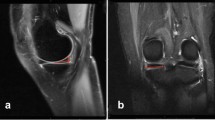

Bone bruises, also known as bone marrow edema-like lesions, are characterized by hemorrhage, edema, necrosis, and fibrosis [8, 14], and are associated with ACL ruptures in up to 80% of the cases [26]. They are defined as areas of increased signal intensity of the bone marrow in T2-weighted MRI images, but are often better identified through fat suppression and short tau inversion recovery (STIR) sequences [2, 12]. The MRI has moderate to high sensitivity in identifying bone bruises, with 97% and 100% sensitivity for the posterior aspect of the lateral tibial plateau and lateral femoral condyle, respectively [8, 14].

MRI images were obtained using 1.5 T (GE SIGMA LX, Milwaukee, USA) scanner and quadrature transmit receive coil. The imaging protocol included sagittal, axial and coronal proton density (PD) weighted fat-saturated fast spin-echo (FSE) images. The PD-weighted fat-saturated FSE images were used to evaluate and quantify bone bruises and to evaluate the meniscus and ligament integrity. The bone bruise volume was measured when present at the medial and lateral femoral condyles and medial and lateral tibial plateaus. All the bone bruise volume measurements were made by the same independent experienced orthopaedic clinician. The area of bone bruise was identified as an area of high signal intensity compared to the low signal intensity surrounding bone. The MRI sequence was uploaded on ImageJ (http://imagej.nih.gov/ij/) to process the MRI slices into pictures and to highlight the bone bruise and record it as the number of pixels included in the selected area. The bone bruise volume (mm3) was calculated using the following formula: number of voxels × voxel volume. The voxel volume was obtained as follows: pixel resolution × slice thickness [18].